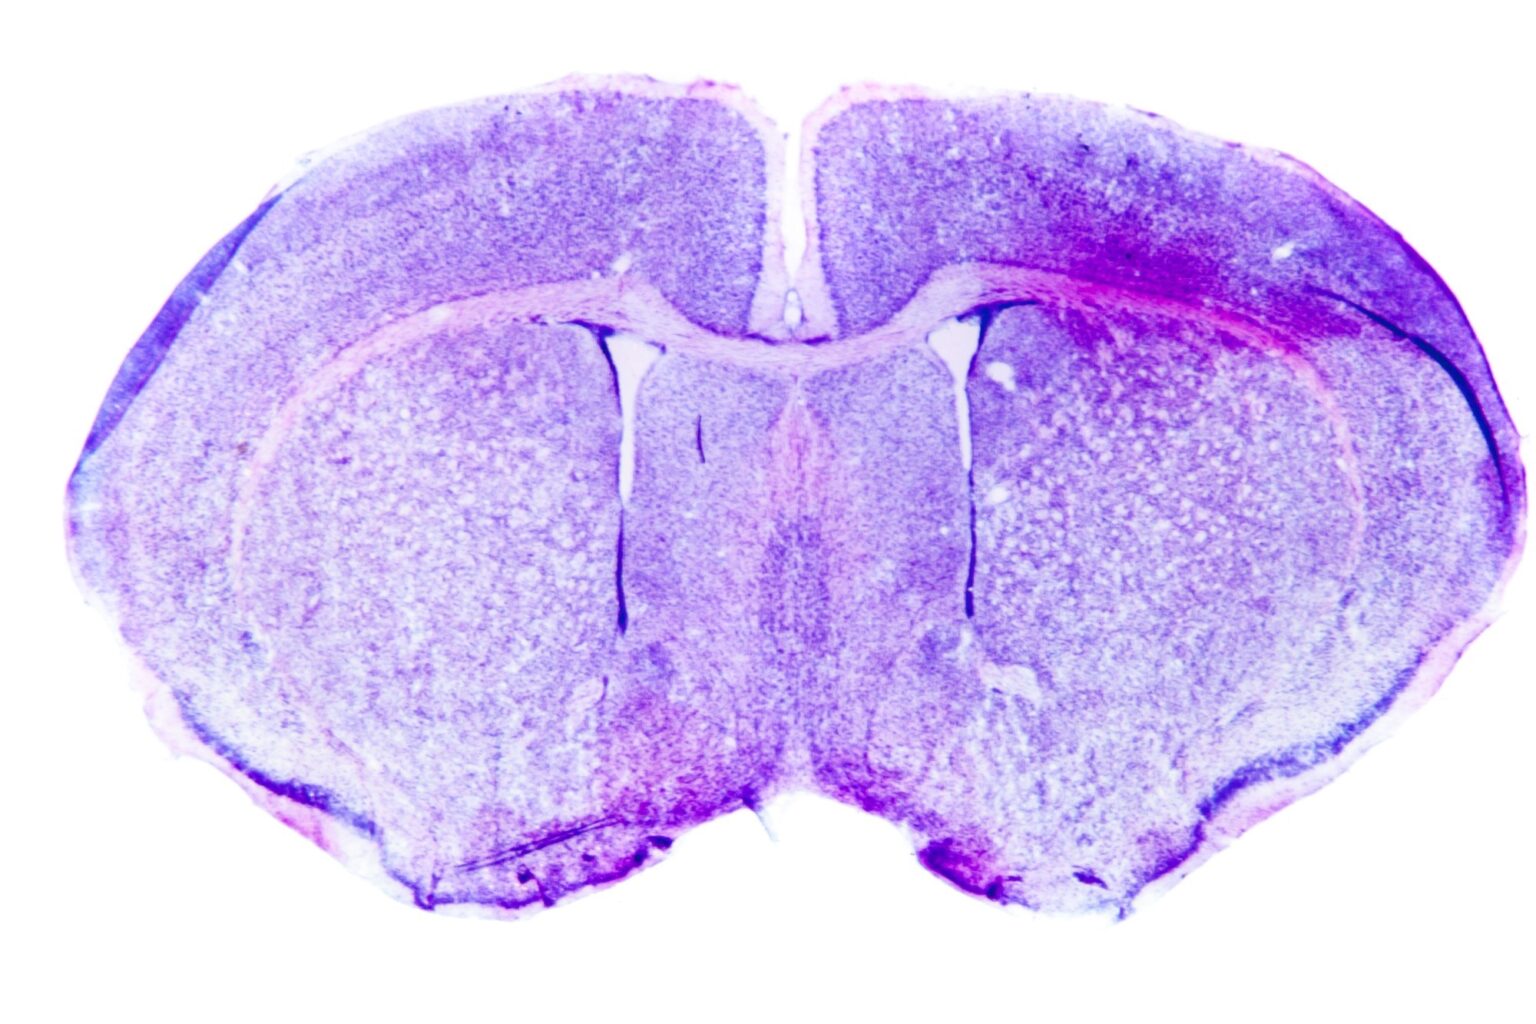

Image Credit: Pan Xunbin/Shutterstock.com